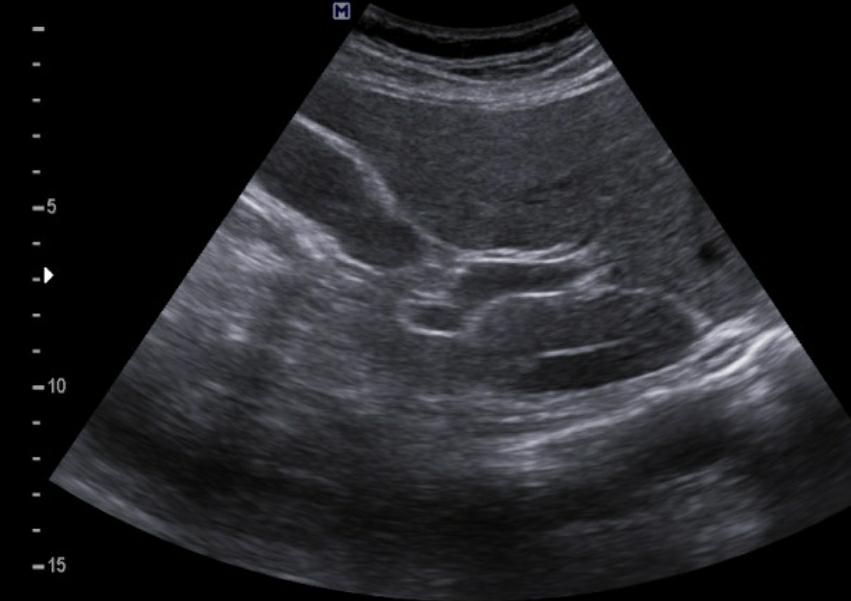

간에 혹이 있는건가요? 초음파 사진 봐주세요

간에 혹이 있는건지 맞다면 크기나 모양이 혈종인지 아이면 암으로 의심이 되는지 초음파 사진 봐주세요...ㅜㅜㅜ꼭 답변 부탁드립니다

• 2번 째 사진

간 초음파로만 봐서는 약간의 지방간이 관찰되지만 혈종으로 의심되지는

않으며 사진 우측에 보이는 동그란 부분은 장의 단면이 관찰되었을 가능성이

높은 것으로 보입니다